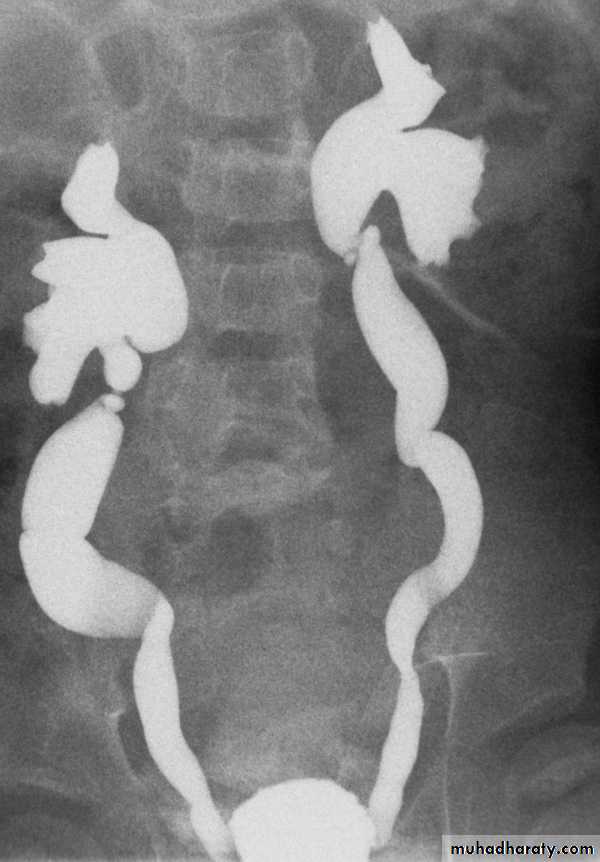

IVU

Large kidney .

Lobulated out-line.

Distortion of pelvi- calyceal system depend on cyst size, number and position.

In advanced cases there is elongation and stretching of minor and major calyces ( spider leg).

In advanced cases IVU shows non-functioning kidney .